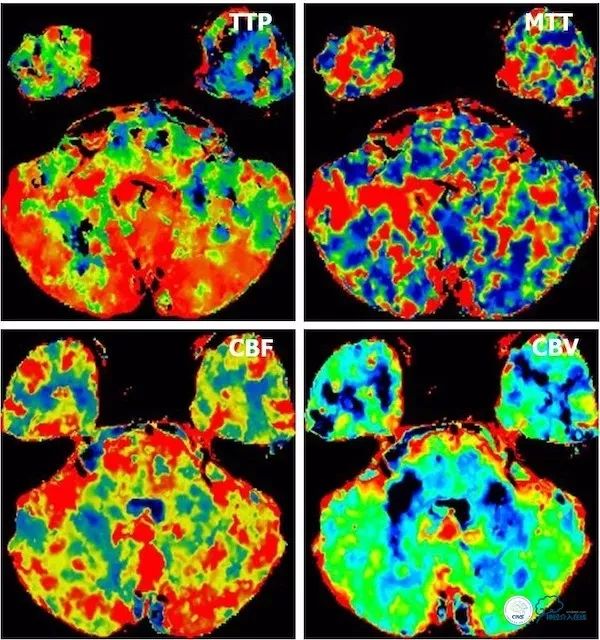

CTP:脑干、小脑低灌注(图9)。

图9

后循环CTP:灌注较前明显改善(图17)。

图17